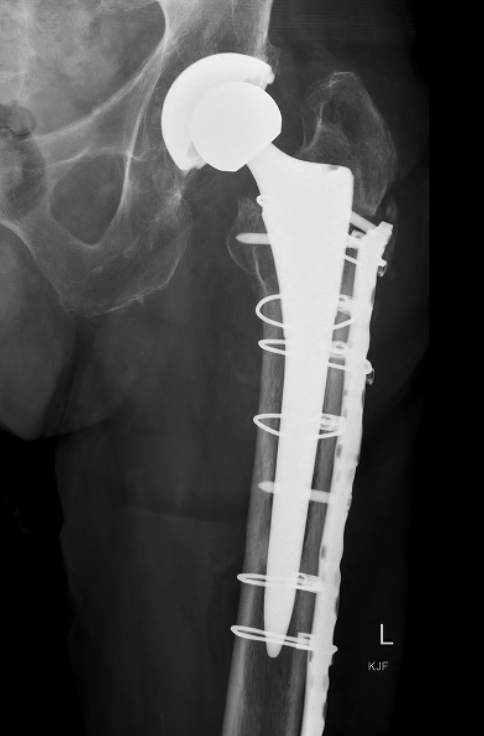

Revision uncemented arthroplasty with Zimmer cable plate

ORIF with locking cable plate and +/- Cortical strut allograft

Plates

Contoured anatomical fit with trochanteric extension

Variable angle locking screws to go around implants

Cable options

Unicortical screw options